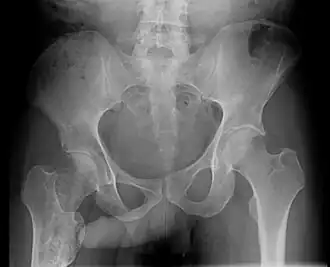

Positive John Thomas sign in patient with right femoral enchondroma

The John Thomas sign,[1] also known as the Throckmorton sign,[2] is a slang or joke term used in the field of radiology. It refers to the position of a penis as it relates to pathology on an X-ray of a pelvis. When the penis (visible on the X-ray as a shadow) points towards the same side as a unilateral medical condition such as a broken bone, this is considered a "positive John Thomas sign," and if the shadow points to the other side, it is a "negative John Thomas sign."[3]